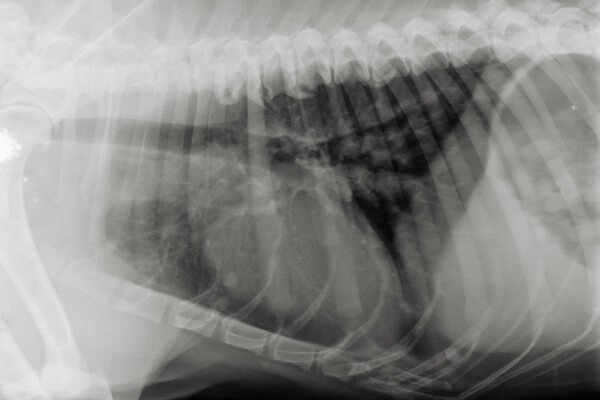

Das Ergebnis ist ein zweidimensionales Schattenbild, das die Tierärztin oder der Tierarzt für diagnostische Zwecke nutzt, beispielsweise bei Erkrankungen des Bewegungsapparates. Auf den Röntgenbildern sind Gewebestrukturen, Veränderungen am Skelett sowie die Lage von Organen oder röntgendichten Fremdkörpern sichtbar. Knochen oder dichte Strukturen erscheinen dabei weiß und Luft – zum Beispiel in der Lunge – sowie Flüssigkeiten dunkel.

Innere Organe lassen sich aufgrund ihrer geringen Dichte weniger gut auf dem Röntgenbild darstellen. Im Brustraum sind sie durch den hohen Kontrast zur schwarzen Lunge dennoch recht gut erkennbar. So können zum Beispiel ein vergrößertes Herz, Tumorerkrankungen, Lungenödeme oder eine Lungenentzündung mittels Röntgen diagnostiziert werden. Es kann unter anderem festgestellt werden, ob sich Flüssigkeit oder Blut in der Lunge gesammelt hat. Auch für die Untersuchung anderer Bereiche des Brustkorbes wie beispielsweise Teile der Speiseröhre oder Zwerchfells wird die Röntgenaufnahme eingesetzt.